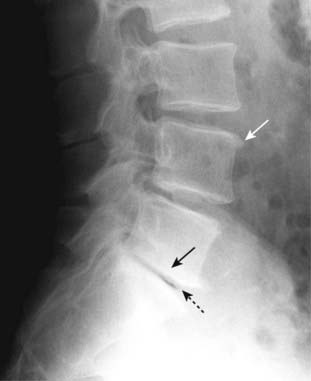

Figure 24-11 Spondylolytic spondylolisthesis (A) and degenerative spondylolisthesis (B).

A, There is forward slippage of L4 on L5 equal to about half the AP diameter of L5 (solid black arrow), so this is classified as a Grade II spondylolisthesis. Spondylolysis is present (solid white arrow) that has allowed the slip to take place. There are also incidental large osteophytes at the corners of the vertebral bodies (dotted black arrow). B, Facet osteoarthritis (solid white arrows) may be associated with spondylolisthesis through a complex interaction between the ligaments, disks, and facet joints. In degenerative spondylolisthesis, there is no break in the pars interarticularis and the degree of spondylolisthesis (solid black arrow) is usually less in this group than in those with spondylolisthesis from bilateral spondylolysis. The L4-L5 disk space is most commonly affected.

imageIn general, spondylolisthesis can occur if there are bilateral breaks in the pars interarticularis (spondylolytic spondylolisthesis) or if there is osteoarthritis of the facet joints (degenerative spondylolisthesis) (Fig. 24-11).

image In degenerative spondylolisthesis, there is no break in the pars interarticularis. The degree of spondylolisthesis is usually less from this etiology than in those with spondylolisthesis from spondylolysis. Degenerative spondylolisthesis is more common in women and usually affects the L4-L5 disk space.

If the slippage approximates 25% of the anteroposterior (AP) diameter of the vertebral body below, it is called a grade I spondylolisthesis. If the slippage approximates 50% of the AP diameter of the vertebral body below, it is called a grade II spondylolisthesis, and so on for grade III and grade IV (see Fig. 24-11).

Spondylolysis is easiest to visualize on an oblique conventional radiograph of the lumbar spine or CT in which a lucency representing the break in the “neck” of the Scottie dog (the “collar” on the Scottie dog) may be seen in the pars interarticularis (Fig. 24-12).